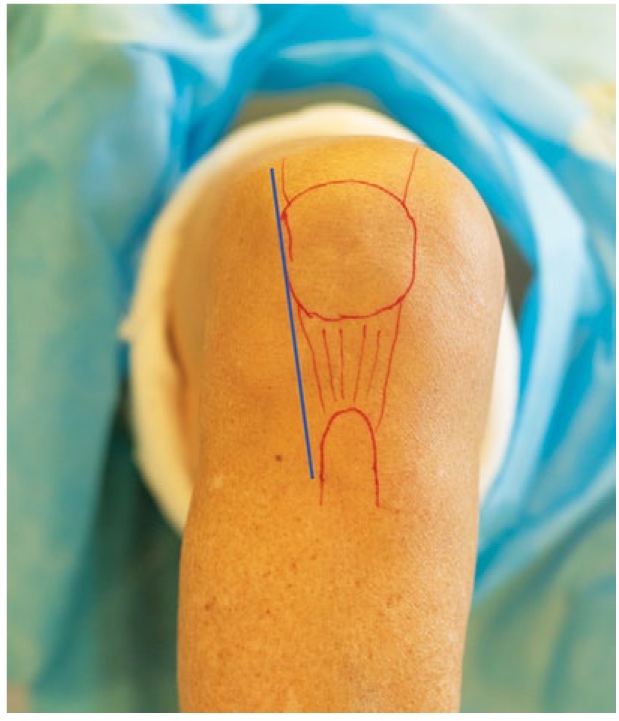

Пациентам выполняют переднелатеральный мини-инвазивный доступ к коленному суставу (рис. 5).

Рис. 5. Предоперационная разметка анатомических ориентиров и схема доступа к коленному суставу

Fig. 5. Preoperative marking of anatomical landmarks and access scheme to the knee joint

Кожный разрез длиной 7–10 см осуществляют по краю надколенника от его верхнего края до латеральной поверхности бугристости большеберцовой кости. В этих же пределах производят латеральную артротомию, обходя надколенник снаружи и формируя при этом несвободный жировой лоскут из тела Гоффа. При этом ножка жирового лоскута остается фиксированной к переднелатеральной части капсулы сустава, что позволяет не нарушать кровоснабжение лоскута за счет сохранения латеральной нижней артерии (рис. 6).